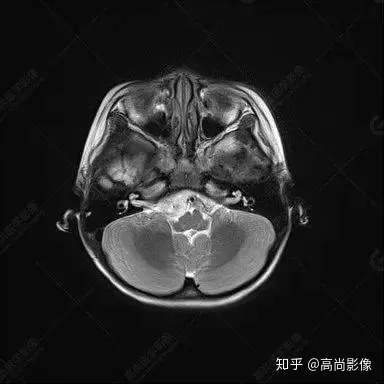

右側(cè)顳葉腫瘤切除術(shù)后(具體不詳):右側(cè)顳部骨質(zhì)不連續(xù)呈術(shù)后改變,右側(cè)顳葉術(shù)區(qū)見片狀長T1長T2信號(hào)影,F(xiàn)LAIR呈低信號(hào);術(shù)區(qū)后方右側(cè)顳枕葉見一巨大占位性病變影,邊界欠清,大小約6.2×5.8×4.3cm(前后×左右×上下),信號(hào)不均勻,T1WI呈等稍低信號(hào)間雜少許高信號(hào),T2WI呈高稍低混雜信號(hào),DWI示部分病灶彌散受限,相應(yīng)ADC圖減低,磁敏感序列見部分呈極低信號(hào),增強(qiáng)掃描可見明顯不均勻強(qiáng)化,鄰近硬腦膜及小腦幕增厚并明顯強(qiáng)化;另延髓右前方及右側(cè)橋小腦角區(qū)見一不規(guī)則形異常信號(hào)影,大小約3.2×1.3×3.7cm(左右×前后×上下),呈長T1稍長T2信號(hào),F(xiàn)LAIR呈等信號(hào),DWI未見受限,增強(qiáng)后明顯均勻強(qiáng)化,鄰近腦膜明顯強(qiáng)化。鄰近腦實(shí)質(zhì)及右側(cè)顳角明顯受壓;左側(cè)大腦半球未見局灶性信號(hào)異常,中線結(jié)構(gòu)稍左移。

右側(cè)顳葉腫瘤切除術(shù)后:現(xiàn)術(shù)區(qū)后方右側(cè)顳枕葉及延髓右前方占位,右側(cè)顳枕部硬腦膜及小腦幕明顯強(qiáng)化,結(jié)合既往影像資料,考慮為胚胎源性惡性腫瘤,如非典型畸胎樣/橫紋肌樣瘤(AT/RT)或原始神經(jīng)外胚層腫瘤(PNET)。